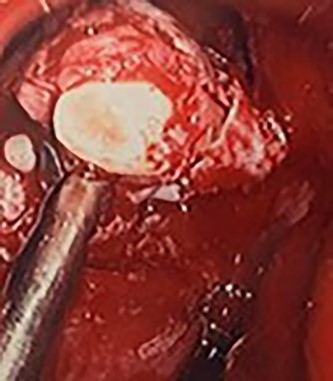

Flexible nasendoscopy offered little in terms of diagnostic benefit. An exam under anesthetic with a view to removing the ectopic tooth via endoscopic sinus surgery was warranted. Right middle turbinate trimming along with a right maxillary antrostomy was performed. The tooth was immediately identified at the antrum as depicted in Figs 4–6. The bony capsule of the tooth was entered and, on manipulation, a second ectopic tooth was identified (Fig. 7) both of which were removed en bloc. The cystic component within the maxillary sinus was marsupilized and extracted. The sinus cavity can be viewed with the utilization of 70° endoscope (Fig. 8). This facilitated bipolar cautery of the base of the cyst and confirmed the absence of an oroantral fistula.

Intra-operative image of the ectopic tooth at the right osteomeatal complex, with curved suction facilitating enucleation.